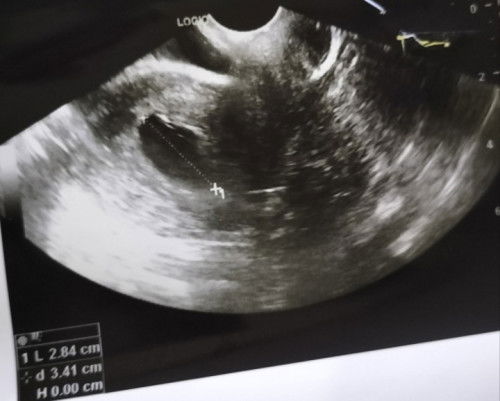

Hai, aku bumil yang divonis hamil kosong / blighted ovum (BO) pada hari sabtu 22/02/25 kemarin. Dan tepat malam tadi 24/02/25 aku harus kuretase. Sedih, tp aku coba kuatkan kalau ini memang yg terbaik. Tanda hamil BO yang aku alami : - usia kandungan berbeda jauh dr usia usg - kantung rahim pertumbuhannya lambat - flek bercak mulai 6 minggu tidak henti walau sudah dikasih penguat rahim - usgtv tgl 16/02/25 kantung janin berukuran 2,3cm, disini dr.obygn ku sudah warning akan kemungkinan hamil kosong. Lalu dijadwalkan untuk cek kembalik di tgl 23/02/25. Tapi, - terjadi perdarahan di tanggal 22/02/25 siang yg cukup banyak hingga akhirnya aku di vonis blighted ovum pada usia kehamilan 9 week dg ukuran kantung rahim 2,84 cm Semangat untuk bumil2 diluar sana yang juga di vonis hamil BO, semoga kita tetap ikhlas dan tegar. Semoga Allah SWT kasih kita kepercayaan-Nya lagi. #firstmom #sharing

Aku hari ini transvaginal, usia kandungan 7 week, ukuran kantung rahim tumbuh nya lambat dan masih kosong. Mohon doanya ya moms sekalian semoga minggu depan udah ada tanda-tanda dedek bayi didalam kantung rahim ku. Ini kehamilan pertama, jujur sedih bgt :'( kata dokter kalau belum ada tanda dedek bayi, kemungkinan hamil kosong/ BO :'( #Sharingdong_Bund #firstmom #sharing #firsttimemom